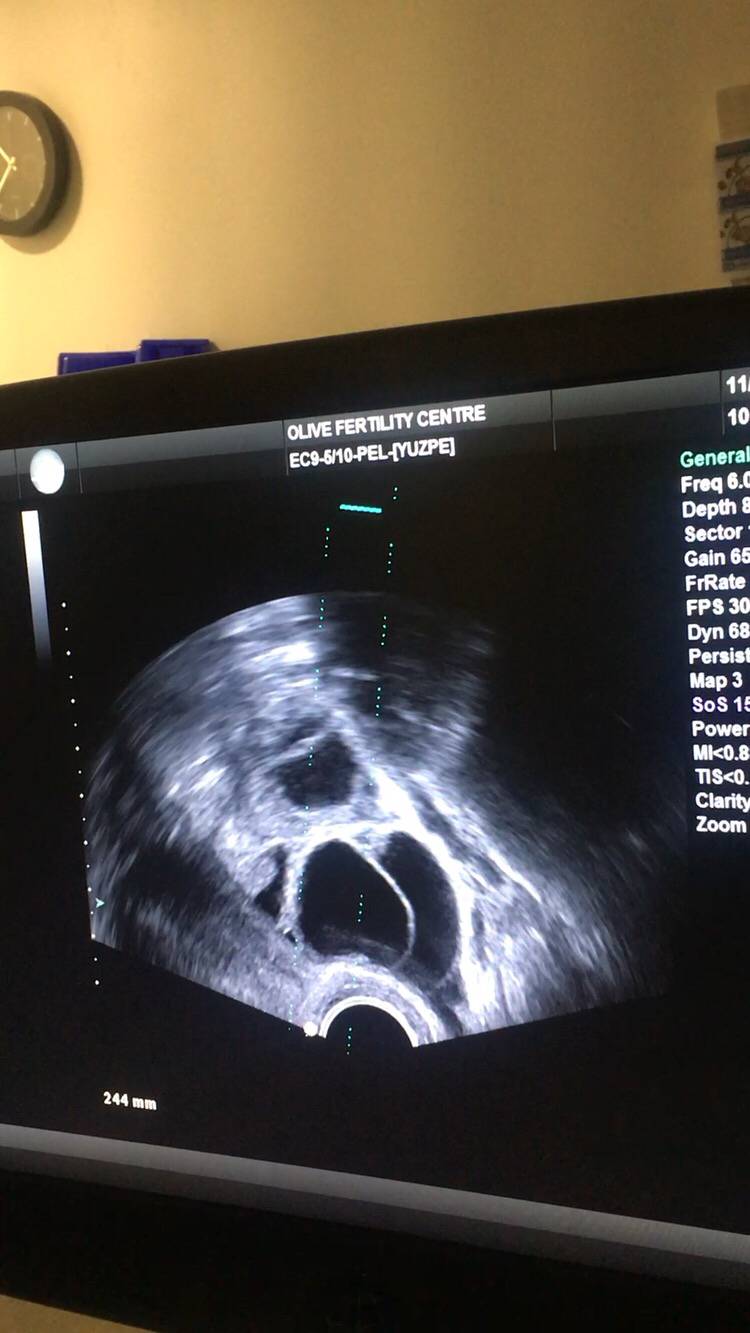

本人女29未婚未育手术前偶尔知道可以冷冻卵子 前提是要在化疗前做大家都知道化疗药物复合卵巢子宫都有一定副作用。一般医生都是建议内分泌药吃五年才可以考虑生孩子 生完继续内分泌五年我自己认为越年轻卵子质量也越好 数量可能也会相对高一点当我五年后34岁 我的卵子还是29岁的状态 而且是未受化疗药物污染的。我觉得为什么不尝试呢以下就来亲说我的取卵过程第一次去咨询的时候做了阴超显示可能有15颗左右卵子第二次是月经来的第二天 又检测了一下卵子 查了血接着自己回家打menopur 75IU ➕ purogan 225IU 每天还要吃一颗来曲挫到第五天的时候去诊所验血 下午通知加打一针orgalutran 接下来的10天左右都是每天定点自己在肚子上打三针 最后五天开始每天检测卵泡大小是否超过17mm到了周一终于不用再打针了 因为周二可以取卵了我没有做全麻 首先做椅子上吃了止痛药 放松的药 还有打了头孢。时间差不多就走去手术室 准备手术术前医生先帮忙清洗下体感觉跟生孩子差不多的姿势 也不知道他弄了些什么 不痛 就是这时候开始打麻药了 有点晕接着正式开始手术 就看到屏幕里一根针插入卵泡把它慢慢吸走 接着换另一个卵泡接着吸一共吸了十分钟 就被告知手术结束了腿上轮椅回到休息室休息了一个小时 并且打了点滴 才让我不那么晕也不想吐了 回家接到电话 取出22枚卵子。成熟的可以冷冻的有9颗好吧虽然一残都没到。但我多了一条后路哪天想生孩子 至少我还有年轻且健康的卵子存在想想心里也舒服点不是么附上我这两周自己给自己打的针 还有最后那些黑黑的球球就是卵泡😁